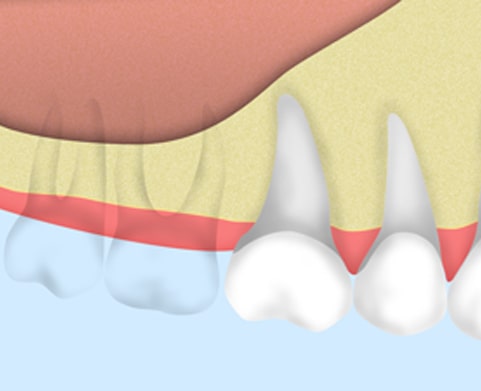

サイナスリフトは上顎の奥歯に骨が少なくなってしまっており、そのままではインプラント治療ができない患者様のための治療、もしくは多くの歯が欠損している時に行う治療法です。インプラントの固定をしやすくするために、移植骨を入れます。

サイナスリフトの進め方

歯槽骨と上顎洞粘膜をはがして、スペースが空いたところに移植骨を埋めていきます。

上顎洞粘膜と歯槽骨の間に10mm以上の移植骨が入りました。

3ヶ月待って骨がしっかりできたら、インプラントを埋めます。